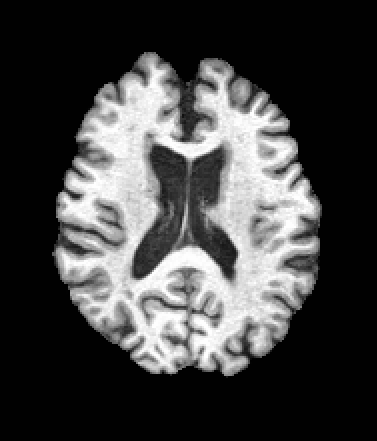

A trained MetaVoxel model can be unconditionally sampled by drawing Gaussian or categorical noise for each variable at timestep , and iteratively apply the denoising network until reaching . Unlike conventional diffusion models that focus solely on image generation, MetaVoxel can generate coherent synthetic patient profiles from the joint distribution , as shown in Figure 2.

| Age: 64.0 | Age: 53.8 | Age: 70.9 | Age: 76.9 |

| Sex: Male | Sex: Female | Sex: Female | Sex: Male |

![]() |

| Age: 80.9 | Age: 77.7 | Age: 73.2 | Age: 84.6 |

| Sex: Male | Sex: Female | Sex: Female | Sex: Female |